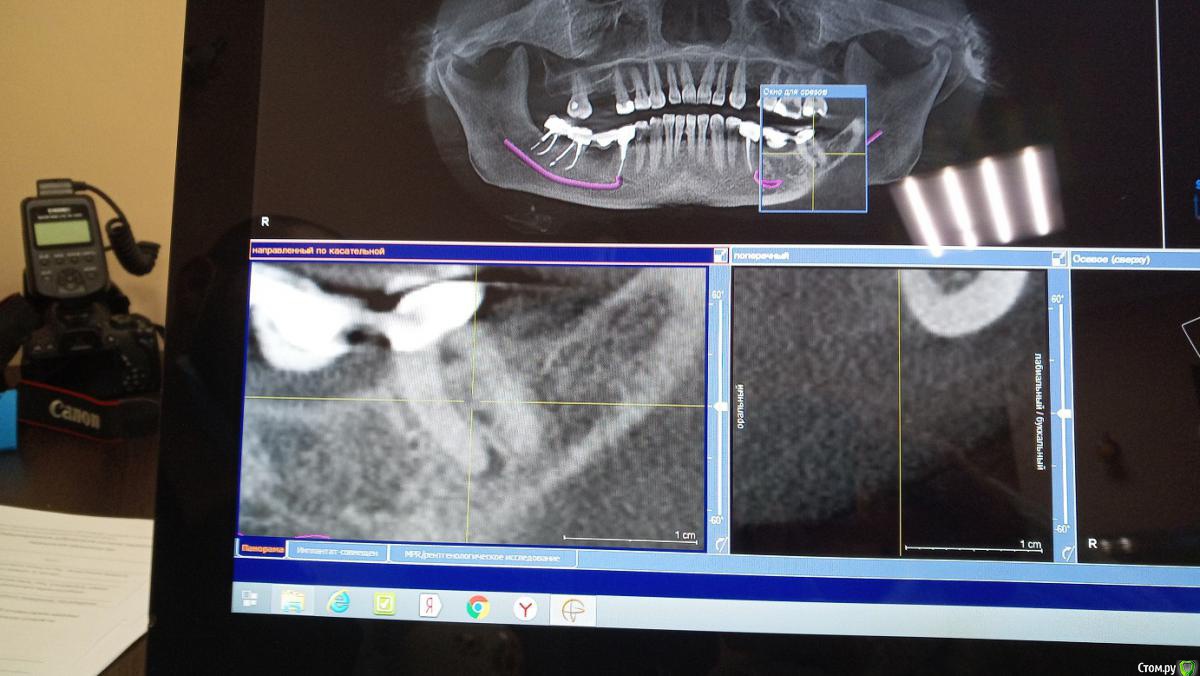

пациент Елена Опубликовано 29 декабря, 2018 Поделиться Опубликовано 29 декабря, 2018 (изменено) Уважаемые доктора, здравствуйте! Если возможно, помогите, пожалуйста, советом. Моей маме 57 лет, в этом году занялась зубами ( изначально диагностировали кисту в гайморовой пазухе справа, в связи с этим пошла на диагностику состояния 17, 15 зубов, 16 удален. Ну и в процессе этого выявилось, что надо лечить почти все). И в общем ситуация возникла такая- на 37 и 35 зубе находился мост, 36 отсутствует. 35 зуб полечили и поставили штифт, 37 врач открыл и пошел в медиальный канал. Пройти не смог, сказал что зуб резорциненный. При этом насколько я поняла по снимку допустил небольшую перфорацию. Сразу зуб закрыл временной пломбой, сказал что однозначно под удаление и имплант. Мама пошла к другому врачу, полечили дистальный канал, его прошли спокойно, сейчас там заложена паста для лечения периодонтита. На снимке КТ видно образование в области медиального канала и между корнями, врач сказал киста. Мама связалась с еще одним доктором ( у которого есть микроскоп), та сказала, что это не киста, а гранулема, сказала, что попробует пройти каналы под микроскопом. Я почитала информацию по этой проблематике и сделала вывод, что раз тот врач, который уже попробовал пройти, не смог и перфорировал, вряд ли это получится и под микроскопом. Верно ли я думаю? Прикрепляю снимки- первый снимок это КТ до попытки лечения, на ней видно эти гранулемы. Второй снимок- это ОПТГ после лечения. Если возможно, помогите пожалуйста с моими вопросами:1)перфорирован ли все таки зуб? я отметила это на снимке цифрой 1 ( на ортопантомограмме после попытки входа в канал)2)Цифрой 2 отметила какое то затемнение на 26 зубе, это тоже подобное образование?3) стоит ли пытаться проходить каналы под микроскопом или лучше не лезть и думать уже над вопросом 4----4) если не полечить- удалять или все таки учитывая небольшой размер и отсутствие клинических проявлений в принципе посидеть на "пороховой бочке", прикрыть это всё недорогим мостом?5) и последний вопрос- нужно ли как то закрывать перфорацию ( если это перфорация)? может быть, как раз это и сделать под микроскопом? Заранее огромное спасибо!! Изменено 29 декабря, 2018 пользователем пациент Елена Ссылка на комментарий